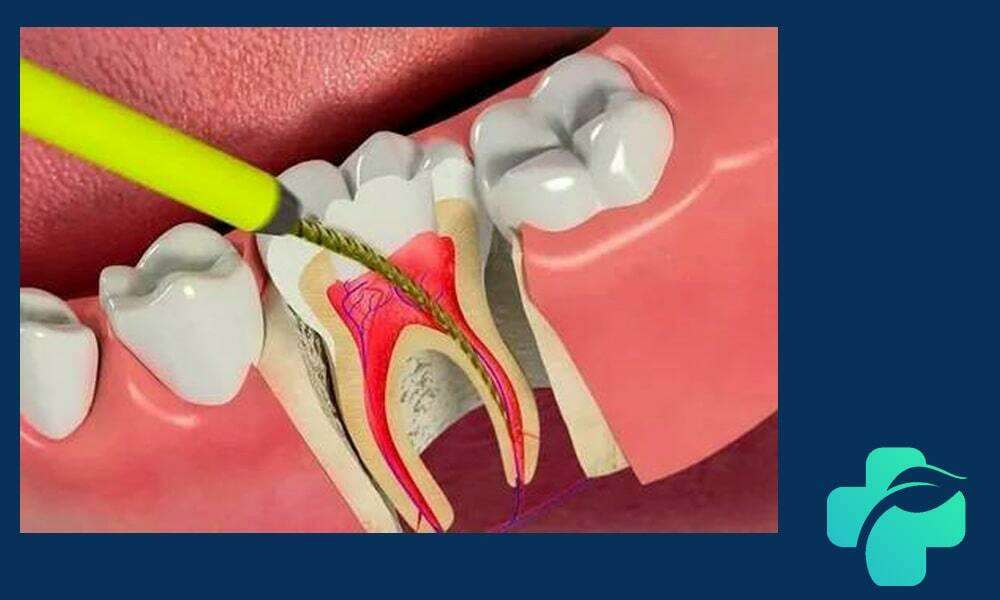

- پاکسازی کانال ریشه: با استفاده از ابزارهای مخصوص، عصب ملتهب یا عفونی تخلیه و کانال های داخلی تمیز می شوند.